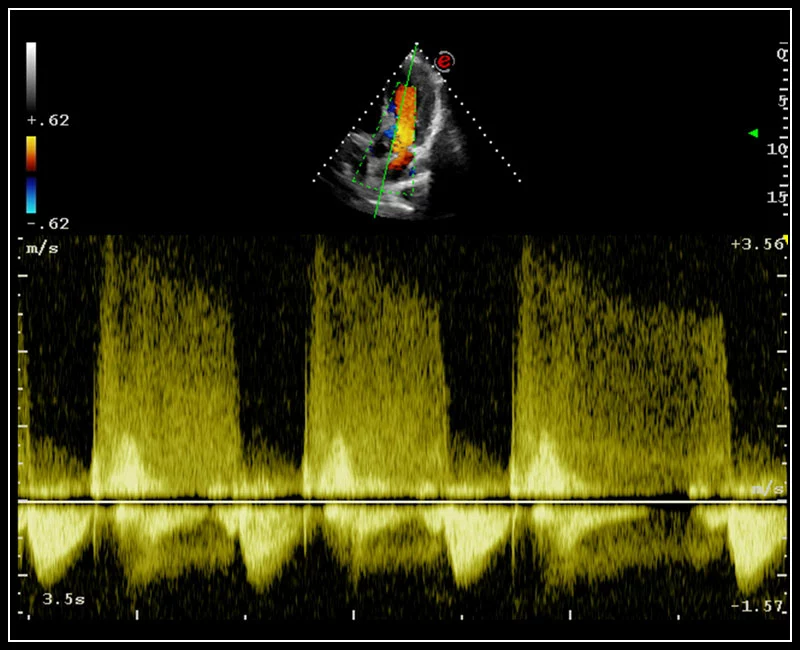

MyLab™C30 - Doppler - CW

MyLab™C30 - Doppler - CW